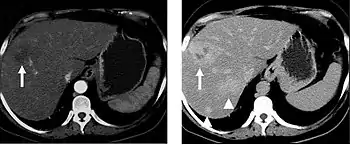

Non-contrast CT scans Figure 1a (left) and 1b (right) are of limited use for the differentiation of soft tissue structures. However, materials like blood, calcium (renal stones, vascular atherosclerosis), bone, and pulmonary parenchyma are highly visible and can usually be adequately assessed with non-contrast CT. For example, in the abdomen and pelvis, there are several indications for non-contrast imaging. These include: evaluation of renal calculi; assessment for gross intra-abdominal hemorrhage; and post-endostent volume measurements. In addition, non-contrast images are often obtained in conjunction with contrast enhanced images in evaluating potential renal transplant donors and in the evaluation of the pancreas (in combination with contrast phases). Of note, dual-energy CT and the development of virtual “non-contrast” images may ultimately obviate the combination scans. Additionally, CT angiography examinations performed for pathologies like aneurysms and dissection are frequently performed in conjunction with non-contrast imaging. The non-contrast images facilitate the differentiation of active extravasation or acute bleeding from vascular calcifications.